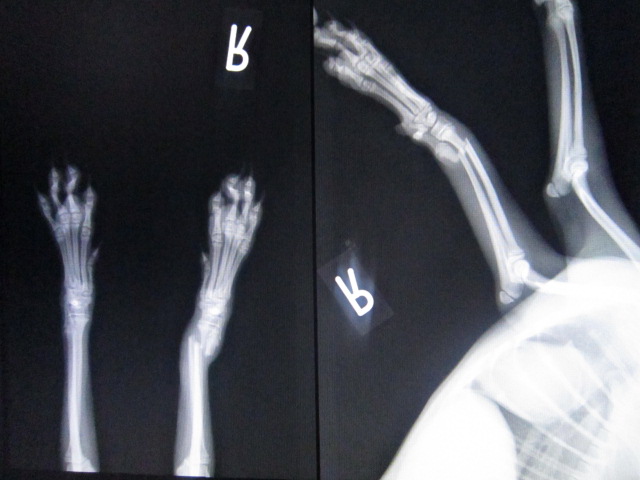

術前のレントゲンです。

右前肢の橈尺骨が明らかに折れています。